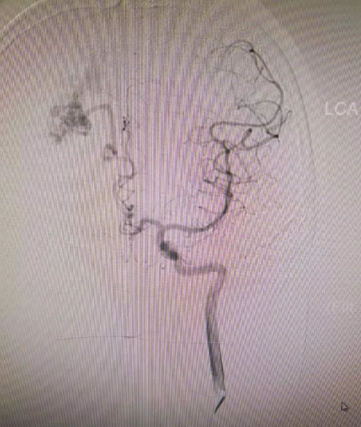

病情简介 主诉: 现病史: 既往史: 体格检查: 家族史: 辅助检查: 头颅CT DSA示供血动脉与引流静脉 右侧椎动脉 左侧颈内动脉造影,左侧大脑中动脉下干供血区动静脉畸形 左侧颈外动脉未向动静脉畸形供血 左侧椎动脉未参与动静脉畸形供血 手术方案: 手术指征: 右侧额顶叶动静脉畸形,左侧颞叶动静脉畸形 手术风险: 栓塞剂返流至颈内动脉导致异位栓塞 术中,术后颅内出血、癫痫等神经功能障碍 治疗过程: 来自大脑前动脉的分支为畸形血管团的一支供血动脉 微导管到位 微导管造影证实在供血动脉 弹簧圈栓塞供血动脉近端防止胶返流,然后注射胶栓塞畸形血管团 大脑前动脉供血的畸形血管团栓塞满意 畸形血管团的另一支供血动脉(来自大脑中动脉的分支) 注射胶栓塞畸形血管团 持续缓慢注射胶,胶逐渐弥散畸形血管团 供应畸形血管团的另一支供血动脉(来自大脑中动脉的另一分支) 持续缓慢注射胶,胶逐渐弥散畸形血管团 畸形血管团接近完全栓塞 标准正侧位造影畸形血管团接近完全栓塞,右侧颈内动脉系统血流通畅,无缺血区域 所用材料: 6F导引导管 ASAHI导丝0.010×200cm Echelon-10非解脱微导管 Apollo可解脱微导管 加奇弹簧圈 Onyx胶 术者思考 脑血管畸形也叫做血管瘤,但并非真肿瘤,是指先天性脑血管的异常发育,在胚胎期时,某些诱导因素导致脑部的血管网未正常发育,进而导致毛细血管发育不全,使动静脉直接相通,并造成短路,最终衍变成为畸形血管团,临床上分为动静脉瘤、先天性颅内囊性动脉瘤、静脉血管瘤及海绵状血管瘤等,其中以动静脉畸形最常见,其发病率达90%以上。脑动静脉畸形根据不同形态可分为以下几类:①动静脉畸形:此类畸形主要由动脉、异常血管、引流静脉组成,血管造影可清晰显示病灶结构,无毛细血管结构,病灶破裂后会引发颅内出血。②发育性静脉畸形:此类畸形主要由髓静脉先天发育异常引起,是目前最常见的一类脑动静脉畸形,一般发生于额顶叶处脑室旁白质或小脑半球处,影像学检查能够发现过度扩张的髓静脉呈扇形汇集至静脉干,两侧动静脉发育程度存在明显差异,髓静脉团形状类似“水母头”。③毛细血管扩张症:此类畸形属于较为罕见的类型,动静脉间毛细血管过度扩张形成团状,病灶较小,CT检查不易发现,一般发生于脑桥、小脑中脚和齿状核等位置。④海绵状血管瘤:此类畸形由大量薄壁血管组成,同样难以通过CT检出,MRI 检测病灶呈“爆米花”状,扫描信号也比较混杂,因其状态不稳定,经常导致反复少量的出血事件发生。临床症状主要为畸形血管破裂出血,“盗血”现象的发生可致局限性脑缺血,从而引起脑萎缩,患者智力会发生减退或出现精神失常。还包括搏动性头痛、癫痫以及偏瘫 、失语等。 其中以出血最为常见,若发生严重出血,出现脑疝,极有可能致死。目前,临床上对于脑血管畸形一般主要有手术切除 、血管内栓塞疗法、γ-刀治疗及放射治疗。作为传统治疗方法,外科手术切除不仅手术风险较高,并且术后患者的神经功能受损的几率较大。近年来,血管内栓塞疗法因其疗效确切、微创、并发症少的优点,已成为治疗脑血管畸形的重要方法。 在早期脑血管畸形治疗过程中,血管内介入栓塞治疗方法常被作为一种辅助性治疗手段在临床上较为广泛的使用,这主要是因为该治疗方法不仅能封闭关键动脉的血液供应,同时也能减少巢的体积,有利于立体定向放射或手术治疗。N-丁基氰基丙烯酸酯(NB-CA)和聚乙烯乙醇是较为传统的血管内介入治疗栓塞材料,目前后者很少使用。由于N-丁基氰基丙烯酸酯将畸形血管团永久封闭,因此,该栓塞材料仍然在临床上较为常见。然而,该材料自身也存在粘性强等缺点,致使很难对大畸形血管团进行较长时间注射,仅能用于注射较小面积的血管团,这也限制了血管内介入栓塞疗法在临床上的广泛使用。近几年来,随着 Onyx栓塞材料的出现,使得动静脉畸形的治疗有了新的突破和进展。作为一种乙烯-乙烯醇共聚物,Onyx栓塞材料是一种非粘附性新型的液体栓塞剂,在治疗动静脉畸形以及动静脉瘘的过程中,该材料能将栓塞剂的注射时间延长,从而增加栓塞面积,这也是目前血管内栓塞疗法在临床上得到推广的主要原因之一 。 术前充分评估bAVM血管构筑、形态学和血流动力学,制定个体化治疗方案是治愈性栓塞策略。研究认为,要最大化发挥可解脱微导管的优势、获得较高治愈性栓塞效果,主要取决于以下条件:①最好选择Spetzler-Martin血管畸形分级Ⅲ级以内、非功能区、终末型供血的致密型畸形团患者;②病灶供血动脉单一、走行平顺,引流静脉位于畸形团外围,较少有动静脉瘘样结构;③对于有Ⅲ级以上多支供血动脉的畸形团,最好予以分次分期栓塞达到治愈,遵循先外围小分支、后中心主干的原则;④可解脱微导管结合近端血流阻断增压技术(PCT)可获得事半功倍效果。 操作时以每分钟0.1 ml的速度向微导管内缓慢注入二甲基亚砜,然后使用Onyx材料进行栓塞。一旦栓塞材料进入至主引流静脉或反流至导管顶端标记处,则应该马上停止栓塞,待栓塞材料分散开后,即可再次进行栓塞操作,反复如此操作,使栓塞材料尽可能在血管内分散,使其完全栓塞。相比较初始造影图像,栓塞完全或分散充分后,即可缓慢拉直微导管,并迅速将其拔出。对于多支动脉供血畸形血管团而言,可行多次造影,并反复进行上述操作 。 BAVM栓塞围手术期可能发生脑出血严重并发症,常见原因包括:①微导管、微导丝操作不当,导致血管破裂;②栓塞时推注压力过大,使畸形血管团破裂;③拔管时畸形血管团明显移位,导致血管断裂;④引流静脉急性或慢性闭塞,导致残余畸形团静脉引流不畅而出血;⑤栓塞术后正常灌注压突破 (NPPB),引发广泛脑出血。如何预防出血并发症,多中心认为:①微导丝应勿进入畸形团内,否则易致出血;一旦发生出血,迅速用50% Glubran胶封堵出血部位。②若有多支供血动脉,不必强求仅通过1支供血动脉获得大范围栓塞,以避免栓塞晚期需要很大推力才能使Onyx胶继续弥散;通过多支路径栓塞更为安全,也减少术中破裂概率。③术中应缓慢推注Onyx胶,以防止向静脉扩散;若出现向静脉弥散立即停止推注,等待20 s后再继续;若引流静脉不再显影,则必须将畸形团彻底栓塞,同时降低基础血压20%,隔30 min复查一次头CT,以早期发现出血迹象。④术前预判治愈性栓塞患者最好应用可解脱微导管,以免拔管时造成血管破裂出血,否则予分期栓塞比较安全;幕下病灶一般供血动脉细小、迂曲,一旦注胶时间过长,为防止拔管时撕裂血管可能需要留置。⑤对于大型高流量病灶或伴发瘘患者,栓塞治疗后如发现引流静脉流速减慢,宜早期CT检查排除脑出血,予以维持全身肝素化1 h,同时控制性降压20%,之后皮下注射5 000 U低分子肝素钙并维持麻醉状态 6~12 h,次日再追加1次,以降低脑出血危险。 该患者年龄小,癫痫起病,诊断为脑动静脉畸形,脑血管畸形是导致患儿脑出血、癫痫的常见神经系统疾病,其致死、致残率高。由于脑 AVM的血管构造和血流动力学复杂,并且儿童的血管较为细小且容易痉挛,儿童身体各器官尚未发育成熟,难以耐受较长时间的手术和术中大量的出血,致使儿童 AVM的手术治疗难度及风险增加。随着诊治技术和材料学的发展,患儿在发病的急性期如得到及时诊治,可挽救生命并长期生存。由于儿童自身发育未完全、神经功能的可塑性强,神经损伤后遗留的功能障碍恢复程度优于成人,或通过训练能得到功能代偿,因此该患者经充分评估后给予介入栓塞治疗,右侧额顶叶大的畸形团接近完全栓塞,左侧颞叶小的畸形团择期治疗。有文献报道,单纯血管内介入栓塞治疗,可引起周围脑组织的水肿,再出血及复发率较手术切除高,因此对于单纯栓塞治疗的AVM 患儿,应进行长期随访和DSA复查。 因血管内介入栓塞治疗存在误栓、栓塞剂反流粘管和断管等不足,一些供血动脉较为细小的AVM 病例中,微导管难以到达畸形团,无法对畸形团进行栓塞,提高手术操作技巧及研发新型的可解脱微导管是解决这一类并发症的关键。研究报道对单支静脉引流、畸形团直径<2 cm BAVM采用静脉途径栓塞,可获得90%治愈率,但存在20%以上出血风险。因此,安全、高效地彻底栓塞BAVM,还需要更多基础研究和临床探索。